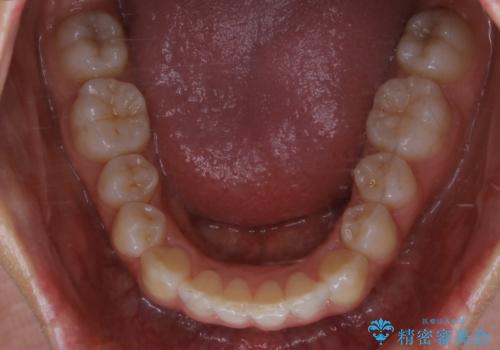

- 上の前歯が大きい事と下の前歯のがたつきを気にされてご相談にいらした方です。上の2番目の歯が矮小歯であったため、矯正治療にて歯のスペースを作った後、矮小歯には被せ物をして前歯のバランスを整えました。

歯科技工士さんとの打ち合わせを重ね、周囲の歯としっかりなじむ天然歯のような被せ物をお作りすることが出来ました。

矯正治療と補綴治療をうまく組み合わせることで、美しい口元に仕上げることが出来ました。矯正治療、補綴治療をまとめて行える総合歯科治療を体現した治療といえます。